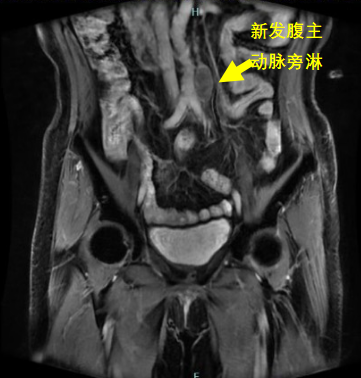

本次參賽病例為一例直腸神經(jīng)內(nèi)分泌癌伴肝轉(zhuǎn)移病灶的老年女性患者,影像科專家評(píng)估分期T3cN1M1,外科專家評(píng)估患者暫無(wú)手術(shù)指征,經(jīng)與腫瘤內(nèi)科專家和放療科專家行MDT會(huì)診后,予患者先行化療?;颊呋驒z測(cè)外送結(jié)果提示患者敏感性較高的化療藥物為:伊立替康和卡培他濱?;颊咝幸晾婵?FU+亞葉酸鈣+貝伐單抗治療4周期后,病情評(píng)估為穩(wěn)定,后患者至放療科行卡培他濱化療聯(lián)合直腸原發(fā)灶局部放療,直腸原發(fā)灶獲得影像學(xué)部分緩解。后患者出現(xiàn)腹主動(dòng)脈旁新發(fā)腫大淋巴結(jié)。再次行病理科、影像科、腫瘤內(nèi)科和放療科多學(xué)科協(xié)作診療,考慮患者為神經(jīng)內(nèi)分泌癌,根據(jù)2023歐洲神經(jīng)內(nèi)分泌腫瘤學(xué)會(huì)推薦轉(zhuǎn)移性消化系統(tǒng)NEC治療以順鉑聯(lián)合依托泊苷為主。并且神經(jīng)內(nèi)分泌癌2024 CSCO指南推薦對(duì)于既往接受過(guò)系統(tǒng)治療且持續(xù)進(jìn)展、缺乏標(biāo)準(zhǔn)治療的轉(zhuǎn)移性NEC患者,也可考慮免疫治療。因此,予患者行依托泊苷聯(lián)合順鉑治療,并且聯(lián)合索凡替尼和恩沃利單抗。兩周期用藥后復(fù)查示腹主動(dòng)脈旁新發(fā)腫大淋巴結(jié)較前明顯縮小,其余病灶穩(wěn)定。 初治時(shí) 直腸病灶放療后出現(xiàn)新發(fā)腹主動(dòng)脈淋巴結(jié) 治療后肝臟病灶穩(wěn)定,直腸原發(fā)灶和腹主動(dòng)脈腫大淋巴結(jié)明顯縮小 王明 主任醫(yī)師 乳腺與腹部腫瘤放療科(放療一科)主任 專業(yè)擅長(zhǎng):各種胸部腫瘤:如乳腺癌、食管癌的放化療、免疫、靶向治療,以及各種腹部腫瘤的放化療,尤其擅長(zhǎng)各種消化道腫瘤:胃癌、肝癌、膽管癌、胰腺癌、結(jié)直腸癌的放療、化療、靶向等綜合治療。泌尿系腫瘤:腎癌、膀胱癌、前列腺癌等腫瘤的綜合治療。 張一擎 主治醫(yī)師 滄州市中心醫(yī)院乳腺與腹部腫瘤放療科(放療一科) 苗玉 副主任醫(yī)師 滄州市中心醫(yī)院病理科 專業(yè)擅長(zhǎng):消化系統(tǒng)腫瘤及消化道早癌篩查病理診斷。 孫敏 副主任醫(yī)師 磁共振成像科 從事臨床工作十多年,對(duì)臨床常見(jiàn)疾病的核磁診斷有豐富的經(jīng)驗(yàn)。 李哲 副主任醫(yī)師 滄州市中心醫(yī)院腫瘤內(nèi)一科 楊立勝 主治醫(yī)師 滄州市中心醫(yī)院結(jié)直腸肛門外科 專業(yè)擅長(zhǎng):結(jié)直腸癌、肛周常見(jiàn)疾病、盆底疾病的外科診療。